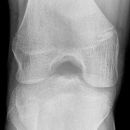

Kniegelenk

Tibiakopf